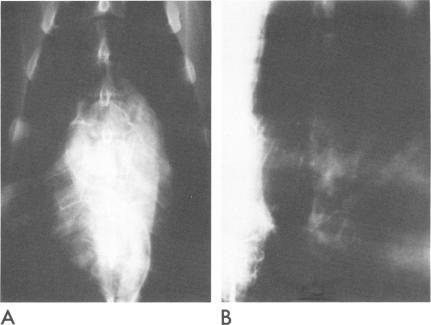

A patient with a dissecting aortic aneurysm, Type 1, developed acute pulmonary edema unexplained by the usual etiologic factors. Pathologic evidence that bronchial arterial circulation was interrupted led us to hypothesize that pulmonary edema could be due to ischemia of the bronchial circulation. To test this hypothesis, two chronic studies were done in dogs. The first study consisted of selective ligation of the right posterior bronchial artery at its origin at the fifth or sixth intercostal artery. After recovery from surgery, biopsies were taken from the ipsilateral and contralateral lung at time periods from 5 hours to 11 days. Ischemic damage was found in seven of eight dogs (87.5%), and was confined to the right lung. Histological examination revealed initial congestion within 8 hours, followed by pulmonary edema within 72 hours, and finally, disruption of alveolar septa with small emphysematous bullae on the eleventh postoperative day. The left lung remained normal in histological appearance. The second study consisted of transplanting the bronchial artery to the pulmonary artery to create a low pressure system and low O(2) content, and to simulate a regional shock situation. In five of six dogs (83.3%), the anastomosis was occluded within 72 hours, probably due to pressure competition from small collateral bronchial circulation. However, in these five dogs, pulmonary vascular resistance increased by 53%, intrapulmonary shunting increased by 83%, and the alveolar-to-arterial oxygen gradient increased by 150 mm Hg. Pulmonary edema was again confined to the right lung. Bronchial arteriograms demonstrated the extensive and variable distribution of the bronchial circulation in dogs. In the sixth dog, the anastomosis remained patent with a left-to-right shunt, due to a larger bronchial arterial collateral circulation. In this animal, the pulmonary arterial resistance, intrapulmonary shunting, and alveolar-arterial O(2) gradient were normal. Pulmonary edema was absent in lung biopsies. Bronchial circulation is discussed with respect to its clinical implications for lung transplants, shock, thoracic aneurysms, and mediastinal surgery. The results of this study suggest that the systemic bronchial circulation is important for normal lung function.

一名患有1型主动脉夹层动脉瘤的患者出现了急性肺水肿,常规病因无法解释该症状。支气管动脉循环中断的病理证据使我们推测肺水肿可能是由于支气管循环缺血所致。为了验证这一假设,我们在狗身上进行了两项慢性研究。第一项研究包括在第五或第六肋间动脉处选择性结扎右后支气管动脉的起始部。手术后恢复后,在5小时至11天的时间段内从同侧和对侧肺取活检组织。8只狗中有7只(87.5%)出现缺血性损伤,且仅限于右肺。组织学检查显示,术后8小时内出现初始充血,72小时内出现肺水肿,最终在术后第11天出现肺泡间隔破坏并伴有小的气肿性肺大泡。左肺组织学外观保持正常。第二项研究包括将支气管动脉移植到肺动脉,以建立一个低压系统和低氧含量,并模拟局部休克状态。6只狗中有5只(83.3%)在72小时内吻合口闭塞,可能是由于小的支气管侧支循环的压力竞争所致。然而,在这5只狗中,肺血管阻力增加了53%,肺内分流增加了83%,肺泡-动脉氧梯度增加了150 mmHg。肺水肿再次仅限于右肺。支气管动脉造影显示了狗支气管循环的广泛和可变分布。在第六只狗中,由于较大的支气管动脉侧支循环,吻合口保持通畅并伴有左向右分流。在这只动物中,肺动脉阻力、肺内分流和肺泡-动脉氧梯度均正常。肺活检中未出现肺水肿。本文讨论了支气管循环在肺移植、休克、胸主动脉瘤和纵隔手术中的临床意义。本研究结果表明,全身支气管循环对正常肺功能很重要。